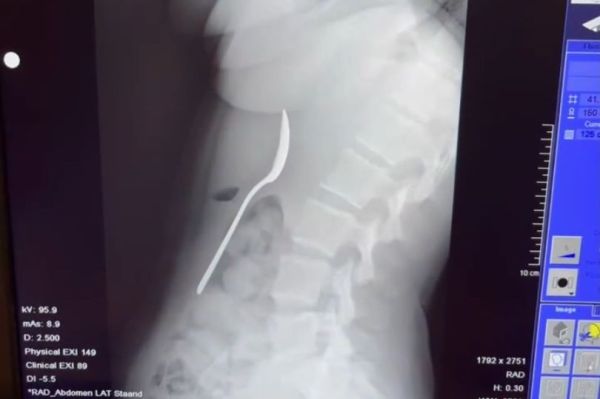

She said: " I didn't feel bad at all – so I didn't say anything about it right away. It wasn't until after dinner that I realised it was actually quite serious. There was a 17cm spoon in my stomach. Online, everywhere said the same thing: go straight to the emergency room. It was only then that I realised how dangerous it could be."

Doctors told her the spoon was too large to pass naturally, so she had to return home and wait until a gastroscopy could be scheduled. Reymy said: "That night was difficult, I felt the spoon moving, sometimes even between my ribs. It was truly terrifying.

The utensil was removed two days later under local anaesthetic. She added: "I wasn’t allowed to swallow while they pulled it up. They had to rotate it in my stomach, which caused a small gastric haemorrhage. It wasn't pleasant, but I felt pure relief when it came out."